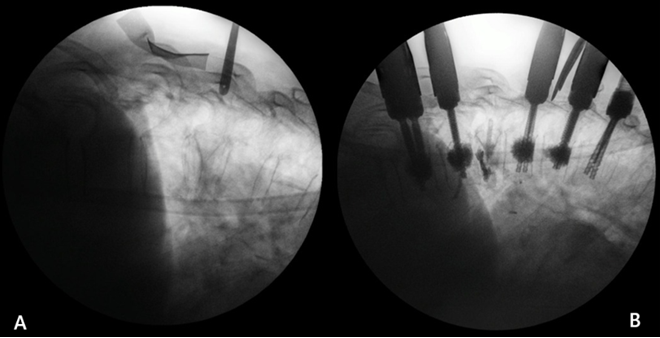

Se realizaron 18 vertebroplastias percutáneas, con la colocación de 4 cm3 de cemento óseo de alta densidad a través de ambos pedículos, introduciendo 2 cm3 en cada lado (90%), 1 fijación transpedicular con cementación (5%) y 1 corpectomía con sustituto vertebral más fijación con cementación (5%). En todas las cirugías se comprobó mediante fluoroscopia la adecuada posición del material o instrumental terapéutico instalado. No se presentaron complicaciones agudas en esta serie de casos (Figura 3).

Figura 3. A) Vista pre y postquirurgica de vertebroplastia. B) Vista pre y postquirúrgica de fijación transpedicular con cementación.